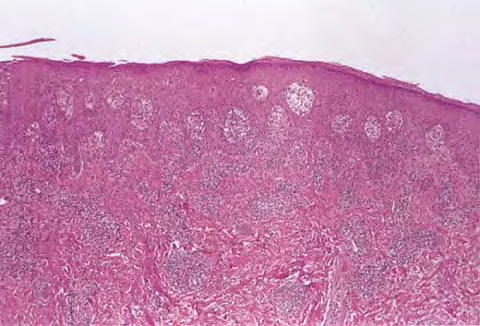

Scondary syphilis = الافرنجي الثانوي